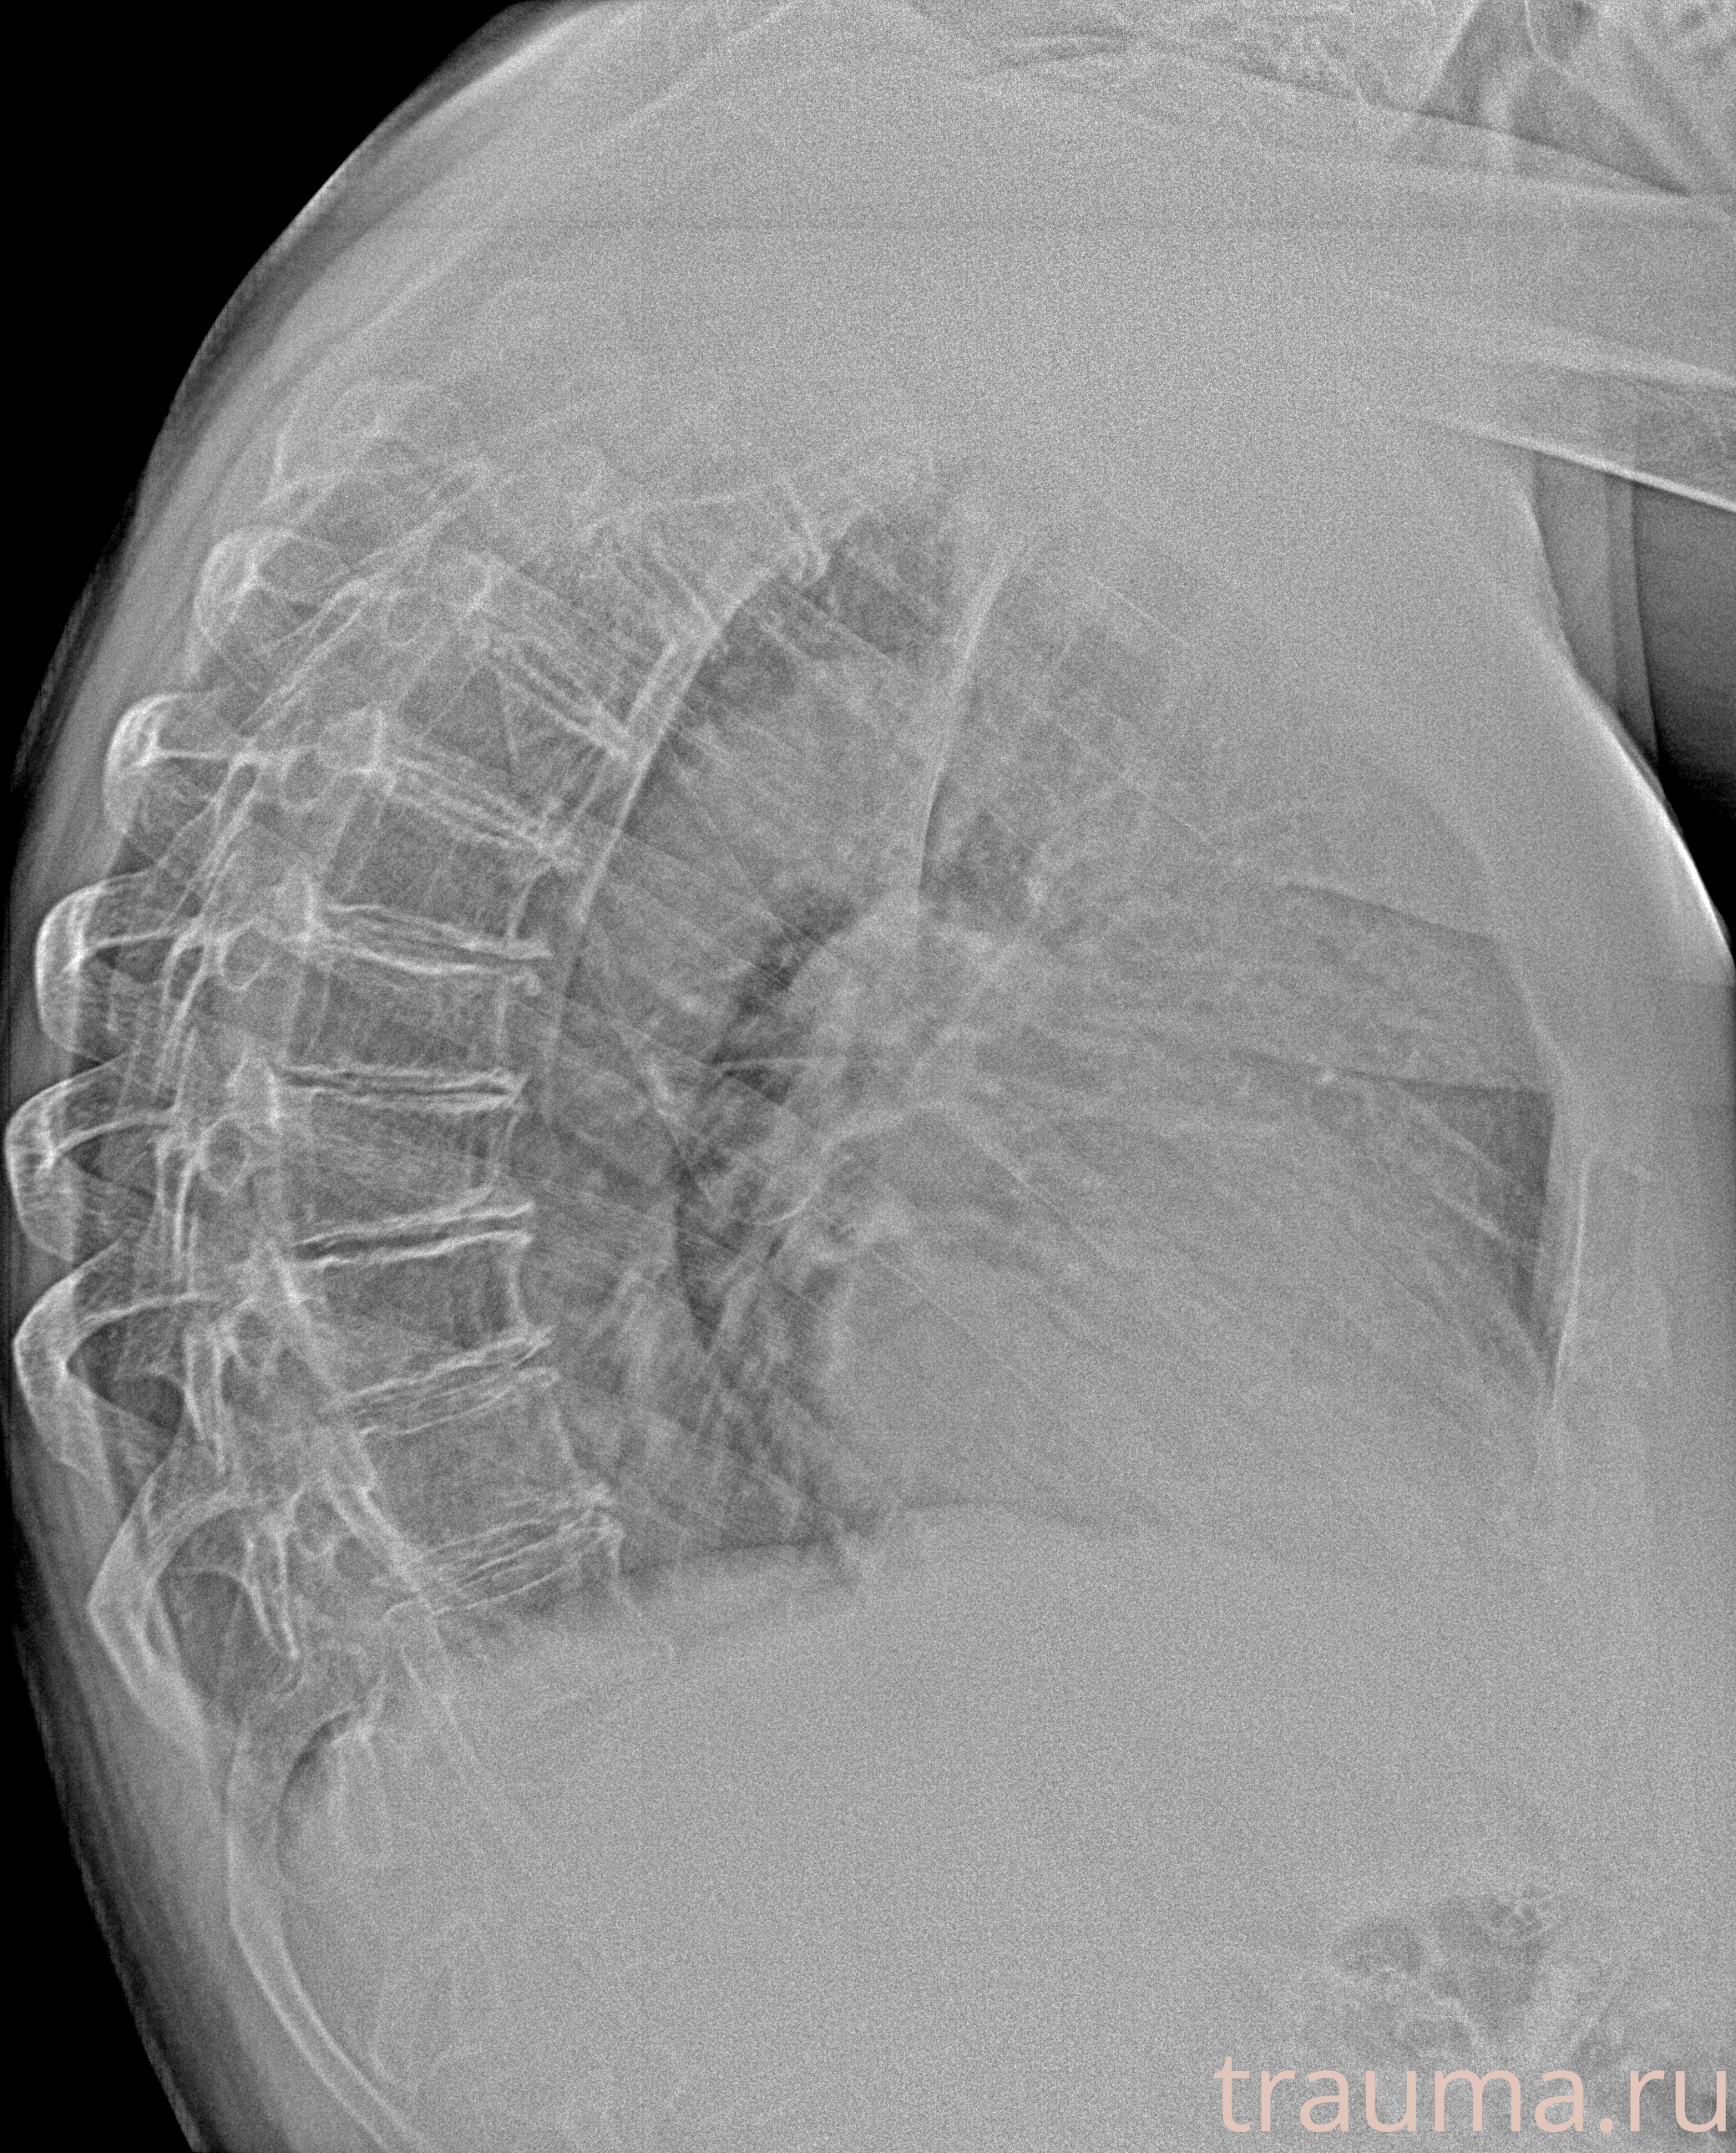

Рентгенограммы

Рентген на дому: по вашему адресу приезжает врач-рентгенолог, травматолог-ортопед с мобильным рентгеновским аппаратом, проводит диагностику травмы или заболевания, делает необходимые рентгенограммы, дает рекомендации по дальнейшему лечению. Получить качественные снимки в домашних условиях возможно благодаря уникальной методике, разработанной МосРентген Центром для института  Склифосовского

при переломе шейки бедра и пневмонии от компании МосРентген Центр - партнера Института имени Склифосовского